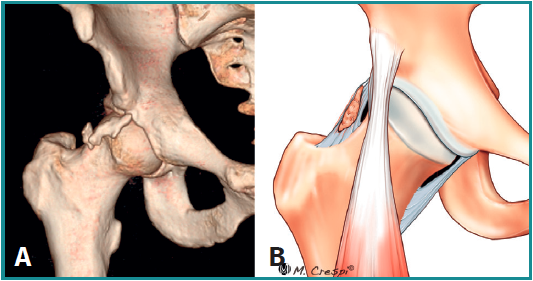

Tipo B: osificación de la porción directa del recto anterior

- Características y morfología radiográfica: en estos casos se visualizará la calcificación cerca del borde superior del acetábulo, generalmente paralela al eje longitudinal del fémur y con 3 posibles variantes: filiforme corto (tipo B1), filiforme largo (tipo B2) y redondeado o difuso (tipo B3)(3)(Figura 6). En los tipos filiformes el aspecto de cola de cometa es característico. Es importante tener en cuenta que existen otras causas de mineralización relacionadas con la porción directa del recto anterior proximal, como las avulsiones de la espina ilíaca anteroinferior o los diferentes tipos de pinzamiento de tipo subespinal.

- Localización y lesiones asociadas: adyacente al borde superior del acetábulo y con deformidades de tipo cam o pincer asociadas en muchos casos.

- Tratamiento: aunque la mayoría de los casos de tendinitis calcificante del recto anterior son autolimitados, los pacientes con molestias moderadas a graves pueden beneficiarse de las opciones de tratamiento no quirúrgico, como el barbotaje guiado por ecografía o TAC o el lavado y la inyección de esteroides. En casos de persistencia de síntomas o la existencia de una calcificación grande, debe ser considerada la extirpación quirúrgica. Las recientes mejoras en la artroscopia de cadera permiten tratar esta patología de una manera menos invasiva que la clásica cirugía abierta por vía anterior, con la ventaja adicional de abordar los trastornos concomitantes intra- y extraarticulares, como el pinzamiento femoroacetabular o subespinal(7,8,9)(Figura 7). Tras la cirugía se debe considerar tratamiento con antiinflamatorios no esteroideos durante 3-6 semanas con el fin de evitar calcificaciones regionales(10).